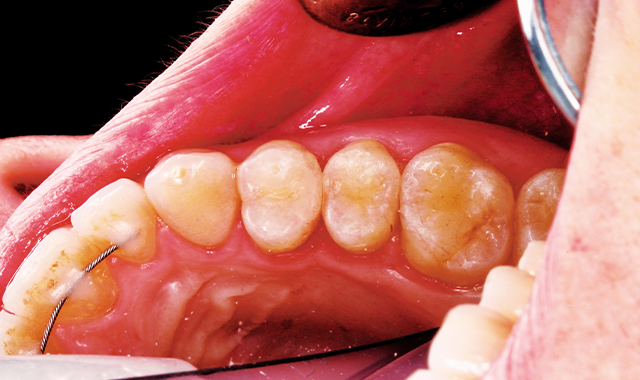

A 32 year-old female patient presented to the practice for her routine examination. The radiographs revealed primary lesions located interproximally (Fig. 1a). The patient was diagnosed with primary caries on tooth #5 DO (Fig. 1b). The clinical objective was to successfully remove caries and restore the tooth while delivering an optimal patient experience.

Fig. 1a Fig. 1b